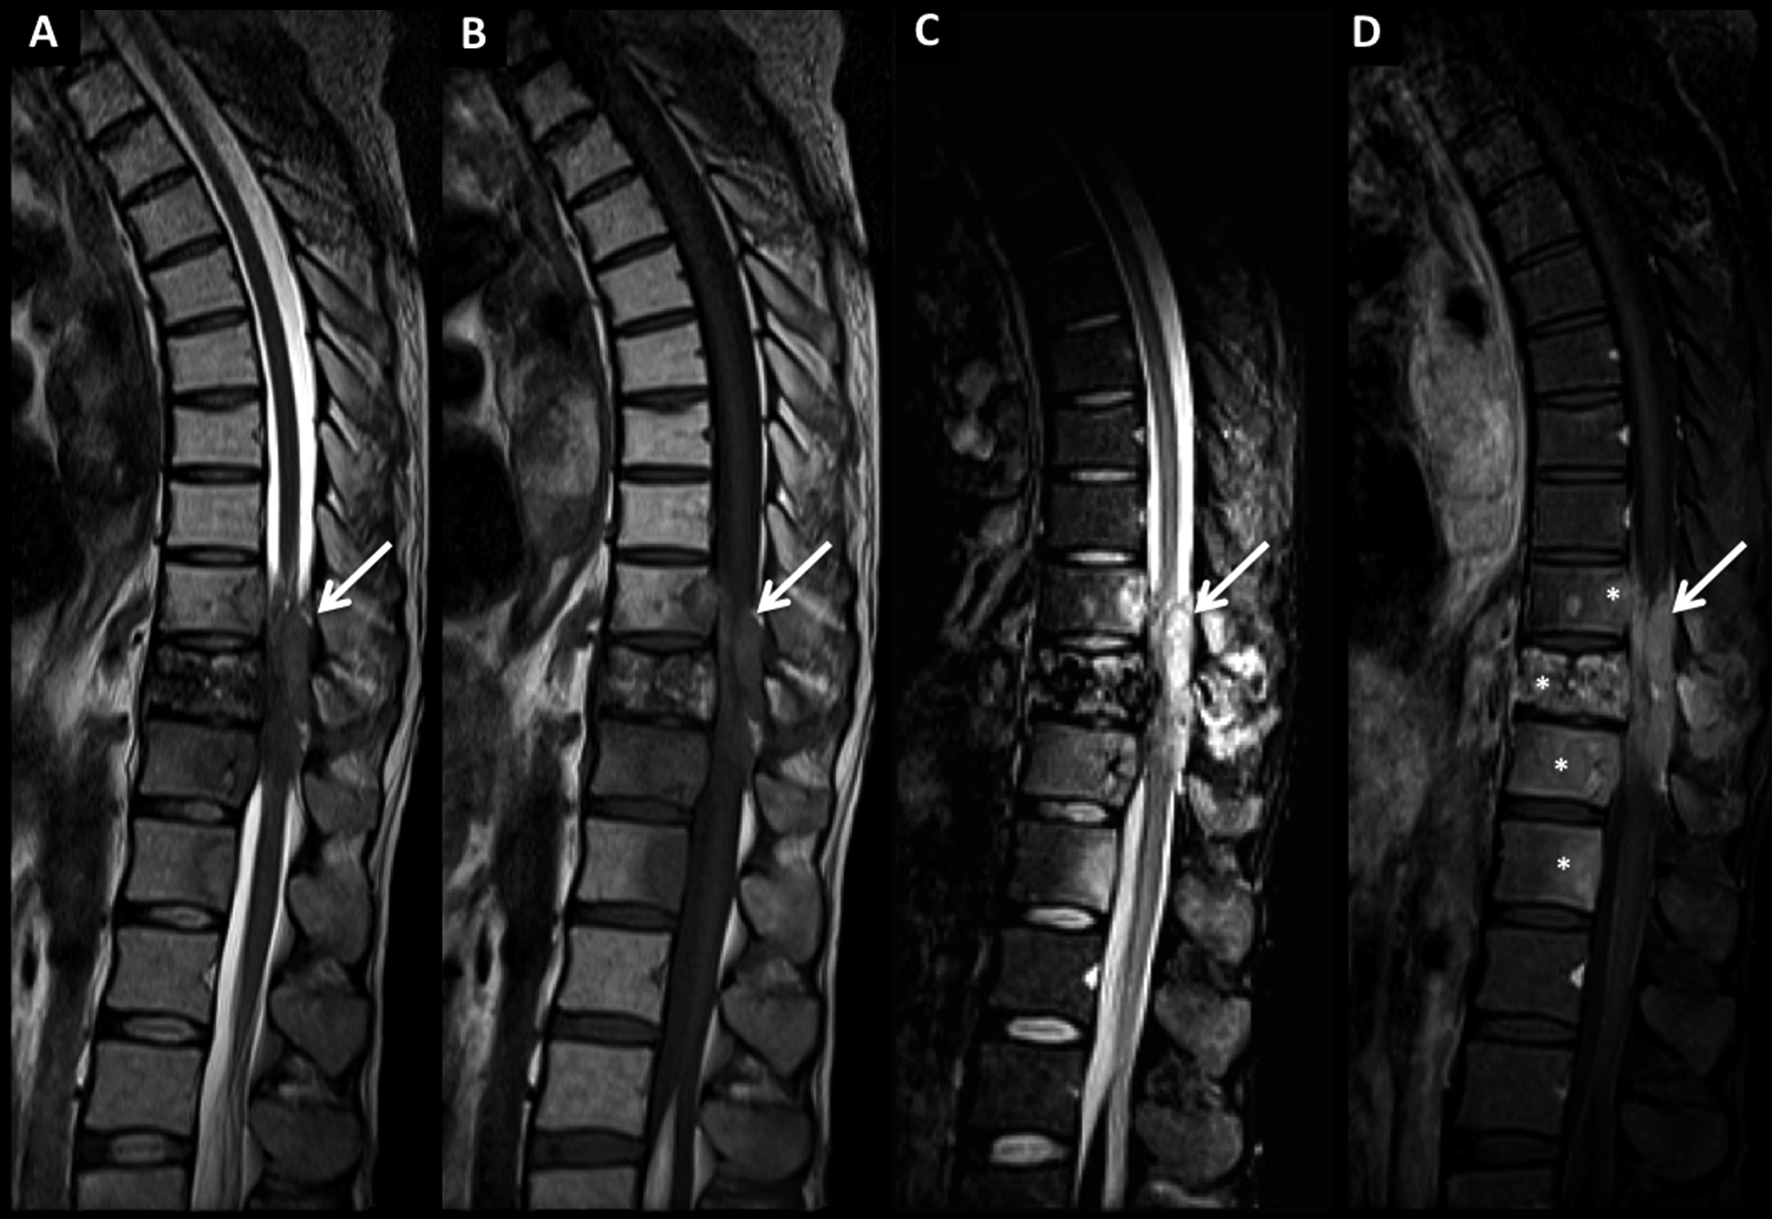

Figura 1

LNH, lesión ósea única, compromiso secundario.

Se muestra el caso de un paciente con LNH sistémico con múltiples adenomegalias retroperitoneales (*) y que en el estudio de estadificación inicial presentó una lesión focal ósea, única, en el cuerpo de T12.

En TC (A) la lesión es claramente lítica, ubicada en el cuerpo vertebral, con escasa esclerosis asociada y con contornos irregulares y destrucción trabecular.

En RM, secuencia SE T1 post-contraste en el plano axial (B) la lesión muestra un centro con necrosis y realce heterogéneo periférico.

LNH, lesión ósea única, compromiso secundario. (cont)

En la secuencia SE T1 sagital (C) la lesión es hipointensa y en STIR (D) es de alta señal con un trazo de fractura asociado de baja señal (flecha discontínua) con extensión del compromiso hacia el pedículo vertebral del mismo lado.

En esta caso no hay aplastamiento vertebral.

La secuencia SE T1 post-contraste con saturación grasa coronal (E) muestra la topografía de la lesión y el patrón de realce.

Se confirma la naturaleza de la lesión por punción ósea guiada por TC.